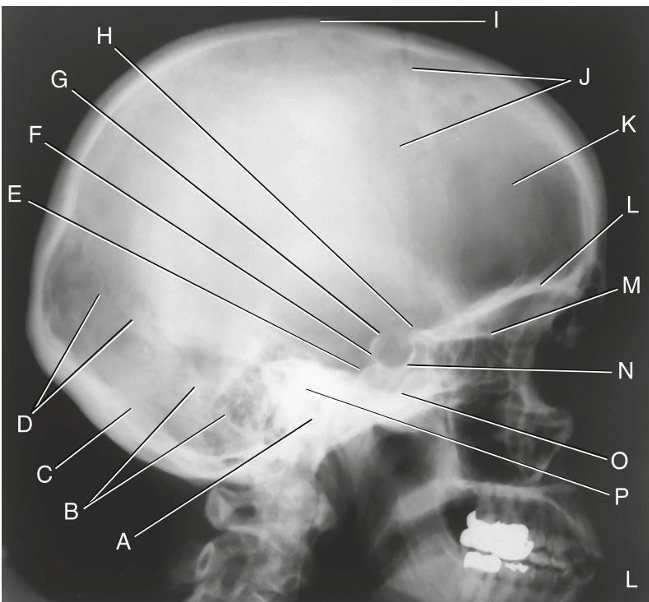

What is A?

External Acoustic (auditory) Meatus - EAM

What is B?

Mastoid portion of temporal bone

What is C?

occipital bone

What is D?

lambdoidal suture

What is E?

clivus

What is F?

dorsum sellae

What is G?

posterior clinoid processes

What is H?

anterior clinoid processes

What is I?

vertex of the cranium

What is J?

coronal suture

What is K?

frontal bone

What is L?

orbital plate

What is M?

cribriform plate

What is N?

sella turcica

What is O?

body of sphenoid (sphenoid sinus)

What is P?

petrous portion of temporal bone